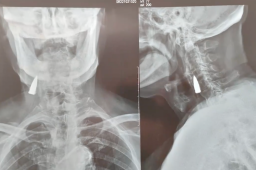

【00:05:00】 10月21日,山东临沂。95岁抗战老兵拍X光,发现颈部遗留一颗子弹头。女婿王先生表示,岳父前一天摔了一跤,去拍X光片发现的子弹头,当时感觉很震惊。

【01:05:00】 10月21日,山东临沂。95岁抗战老兵拍X光,发现颈部遗留一颗子弹头。女婿王先生表示,岳父前一天摔了一跤,去拍X光片发现的子弹头,当时感觉很震惊。

【02:05:00】 10月21日,山东临沂。95岁抗战老兵拍X光,发现颈部遗留一颗子弹头。女婿王先生表示,岳父前一天摔了一跤,去拍X光片发现的子弹头,当时感觉很震惊。

【03:05:00】 10月21日,山东临沂。95岁抗战老兵拍X光,发现颈部遗留一颗子弹头。女婿王先生表示,岳父前一天摔了一跤,去拍X光片发现的子弹头,当时感觉很震惊。

【04:05:00】 10月21日,山东临沂。95岁抗战老兵拍X光,发现颈部遗留一颗子弹头。女婿王先生表示,岳父前一天摔了一跤,去拍X光片发现的子弹头,当时感觉很震惊。

【05:05:00】 10月21日,山东临沂。95岁抗战老兵拍X光,发现颈部遗留一颗子弹头。女婿王先生表示,岳父前一天摔了一跤,去拍X光片发现的子弹头,当时感觉很震惊。

【06:05:00】 10月21日,山东临沂。95岁抗战老兵拍X光,发现颈部遗留一颗子弹头。女婿王先生表示,岳父前一天摔了一跤,去拍X光片发现的子弹头,当时感觉很震惊。

【07:05:00】 10月21日,山东临沂。95岁抗战老兵拍X光,发现颈部遗留一颗子弹头。女婿王先生表示,岳父前一天摔了一跤,去拍X光片发现的子弹头,当时感觉很震惊。

【08:05:00】 10月21日,山东临沂。95岁抗战老兵拍X光,发现颈部遗留一颗子弹头。女婿王先生表示,岳父前一天摔了一跤,去拍X光片发现的子弹头,当时感觉很震惊。

【09:05:00】 10月21日,山东临沂。95岁抗战老兵拍X光,发现颈部遗留一颗子弹头。女婿王先生表示,岳父前一天摔了一跤,去拍X光片发现的子弹头,当时感觉很震惊。

【10:05:00】 10月21日,山东临沂。95岁抗战老兵拍X光,发现颈部遗留一颗子弹头。女婿王先生表示,岳父前一天摔了一跤,去拍X光片发现的子弹头,当时感觉很震惊。

【11:05:00】 10月21日,山东临沂。95岁抗战老兵拍X光,发现颈部遗留一颗子弹头。女婿王先生表示,岳父前一天摔了一跤,去拍X光片发现的子弹头,当时感觉很震惊。

【13:05:00】 10月21日,山东临沂。95岁抗战老兵拍X光,发现颈部遗留一颗子弹头。女婿王先生表示,岳父前一天摔了一跤,去拍X光片发现的子弹头,当时感觉很震惊。